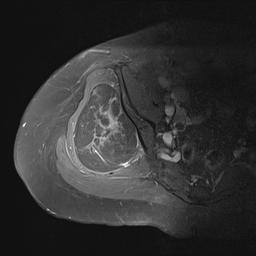

Liposarcoma

MRI

Deep to fascia / heterogenous

Liposarcoma Buttock MRILiposarcoma 2LS 2

Liposarcoma XrayLiposarcoma Buttock MRILiposarcoma MRI 2